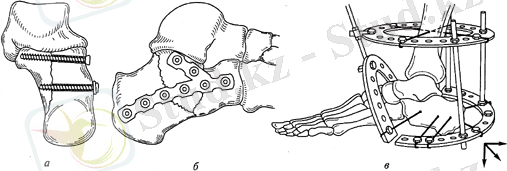

Оперативті ем. Ашық әдіс-енгіш фиксаторлардың көмегімен жүргізіледі (біз, винт, сүйек трансплантаттары, моделдеуші пластиналар) Жақсы нәтижені сыртқы бекітуші аппараттар береді, себебі оның көмегімен ығысуды қалпына келтіреді және аяққа ерте күш түсіруге болады(9 сурет)

9-сурет: Өкше сүйегінің остеосинтезі

А-винтпен, б-моделдеуші пластинамен, в-бізді аппаратпен, г-өкше сүйегінің буынішілік компрессионды сынығы: пластинамен остеосинтезге дейін және кейін